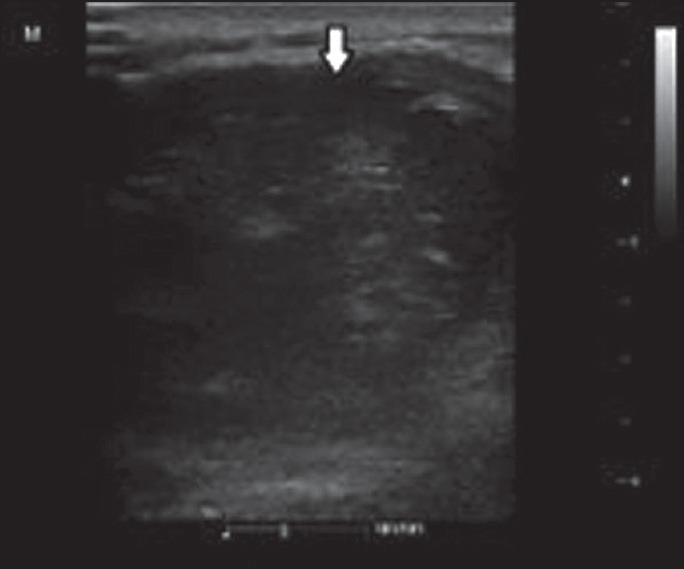

The present article reports two cases that presented to our hospital with the complaint of shoulder pain and had a soft tissue mass affecting the muscles of the rotator cuff and invading the neighboring bone compartments. One of the patients developed mucoepidermoid cancer metastasis of the submandibular gland, and the other was found to have a malignant epithelial tumor metastasized from the lower lobe of the right lung, whose primary origin could not be diagnosed until the imaging examinations were employed. Ultrasound and magnetic resonance imaging findings are presented in this paper.

Metastases to the muscle tissues could be misdiagnosed as primary sarcomas. Because the therapy regiments and prognoses are fairly different for these two entities, the possibility of a metastasis to the muscle tissue must be considered as a differential diagnosis for case of painful soft tissue mass. Ultrasound is very useful in detection of the lesion and acts as a very important tool during guidance for biopsy. Magnetic resonance imaging, however, is a very valuable asset in the evaluation of the borders of the soft tissue mass and its invasive effect on the bony tissues. Particularly when the features such as lobulated contours, peripheral edema, and intratumoral necrosis exist, the possibility of metastases must be considered.

本文报告了两例因肩部疼痛前来我院就诊的病例,均有软组织肿块,累及肩袖肌肉并侵犯邻近骨腔。其中一例患者为下颌下腺黏液表皮样癌转移,另一例患者被发现是右肺下叶转移的恶性上皮性肿瘤,在采用影像学检查之前无法诊断其原发灶。本文展示了超声和磁共振成像的检查结果。

肌肉组织转移可能被误诊为原发性肉瘤。由于这两种疾病的治疗方案和预后有很大差异,对于有疼痛性软组织肿块的病例,必须考虑肌肉组织转移的可能性作为鉴别诊断。超声在检测病变方面非常有用,并且在活检引导过程中是非常重要的工具。然而,磁共振成像在评估软组织肿块的边界及其对骨组织的侵袭作用方面是非常有价值的。特别是当存在分叶状轮廓、周边水肿和瘤内坏死等特征时,必须考虑转移的可能性。